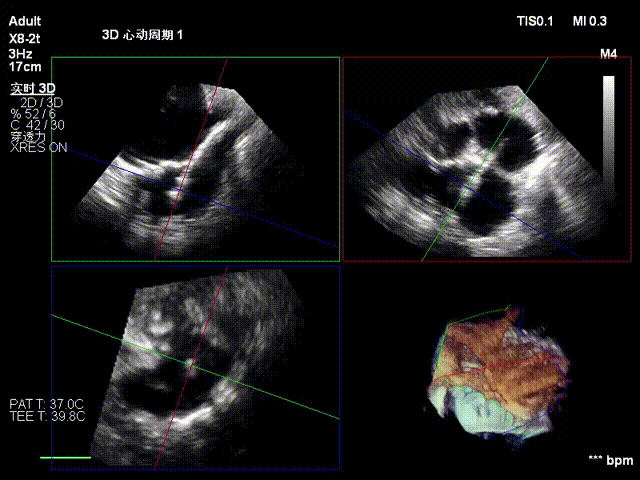

经右颈内静脉穿刺建立通路,置入18Fr鞘管,将K-Clip®输送系统送达右心房。依托三维经食管超声心动图(3D TEE)联合 DSA 双模态引导,经验精准定位瓣环,于后隔交界(P-S commissure)植入14T规格K-Clip®,前后交界(A-P commissure)植入16T规格K-Clip®,实现瓣环多点精准环缩。每枚夹子释放后,团队实时通过超声评估瓣叶对合及反流改善情况,严格遵循 “精准定位 - 锚定验证 - 安全解离” 的规范化操作流程,确认无瓣叶损伤、瓣口狭窄及心包并发症后,完成器械解离与撤出。

5. 第二枚夹子同样操作,三维下夹子形态稳定

1. 瓣环面积由18.7降至11.9,瓣环面积减少36%。

2. 术前反流4+降至1+。